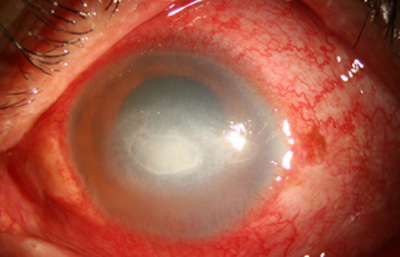

Superficie corneal irregular y grisácea, (Fig. 1, 2) con opácidades granulares en parche y formación de líneas epiteliales elevadas de aspecto granular (Fig. 3), que pueden arborizar dando imágenes de pseudodendritas. Opacidades superficiales satélites. (Figura 4) Inyección ciliar. Ulceración epitelial variante. (Figura 5).

En su evolución se observará aumento del edema, agrandamiento y coalescencia de los infiltrados formando un anillo, (Figura 9, 10 y 11) que progresa hacia la formación de un absceso (Figura 12, 13 y 14), queratolisis superficial, adelgazamiento y perforación corneal (Figura 15 y 16).

Limbitis y escleritis anterior difusas.

En los estados avanzados con abscesificación y queratolisis, se enmascara el cuadro corneal, ocultando las características clínicas típicas de la queratitis por Acanthamoeba. (Fig 18)